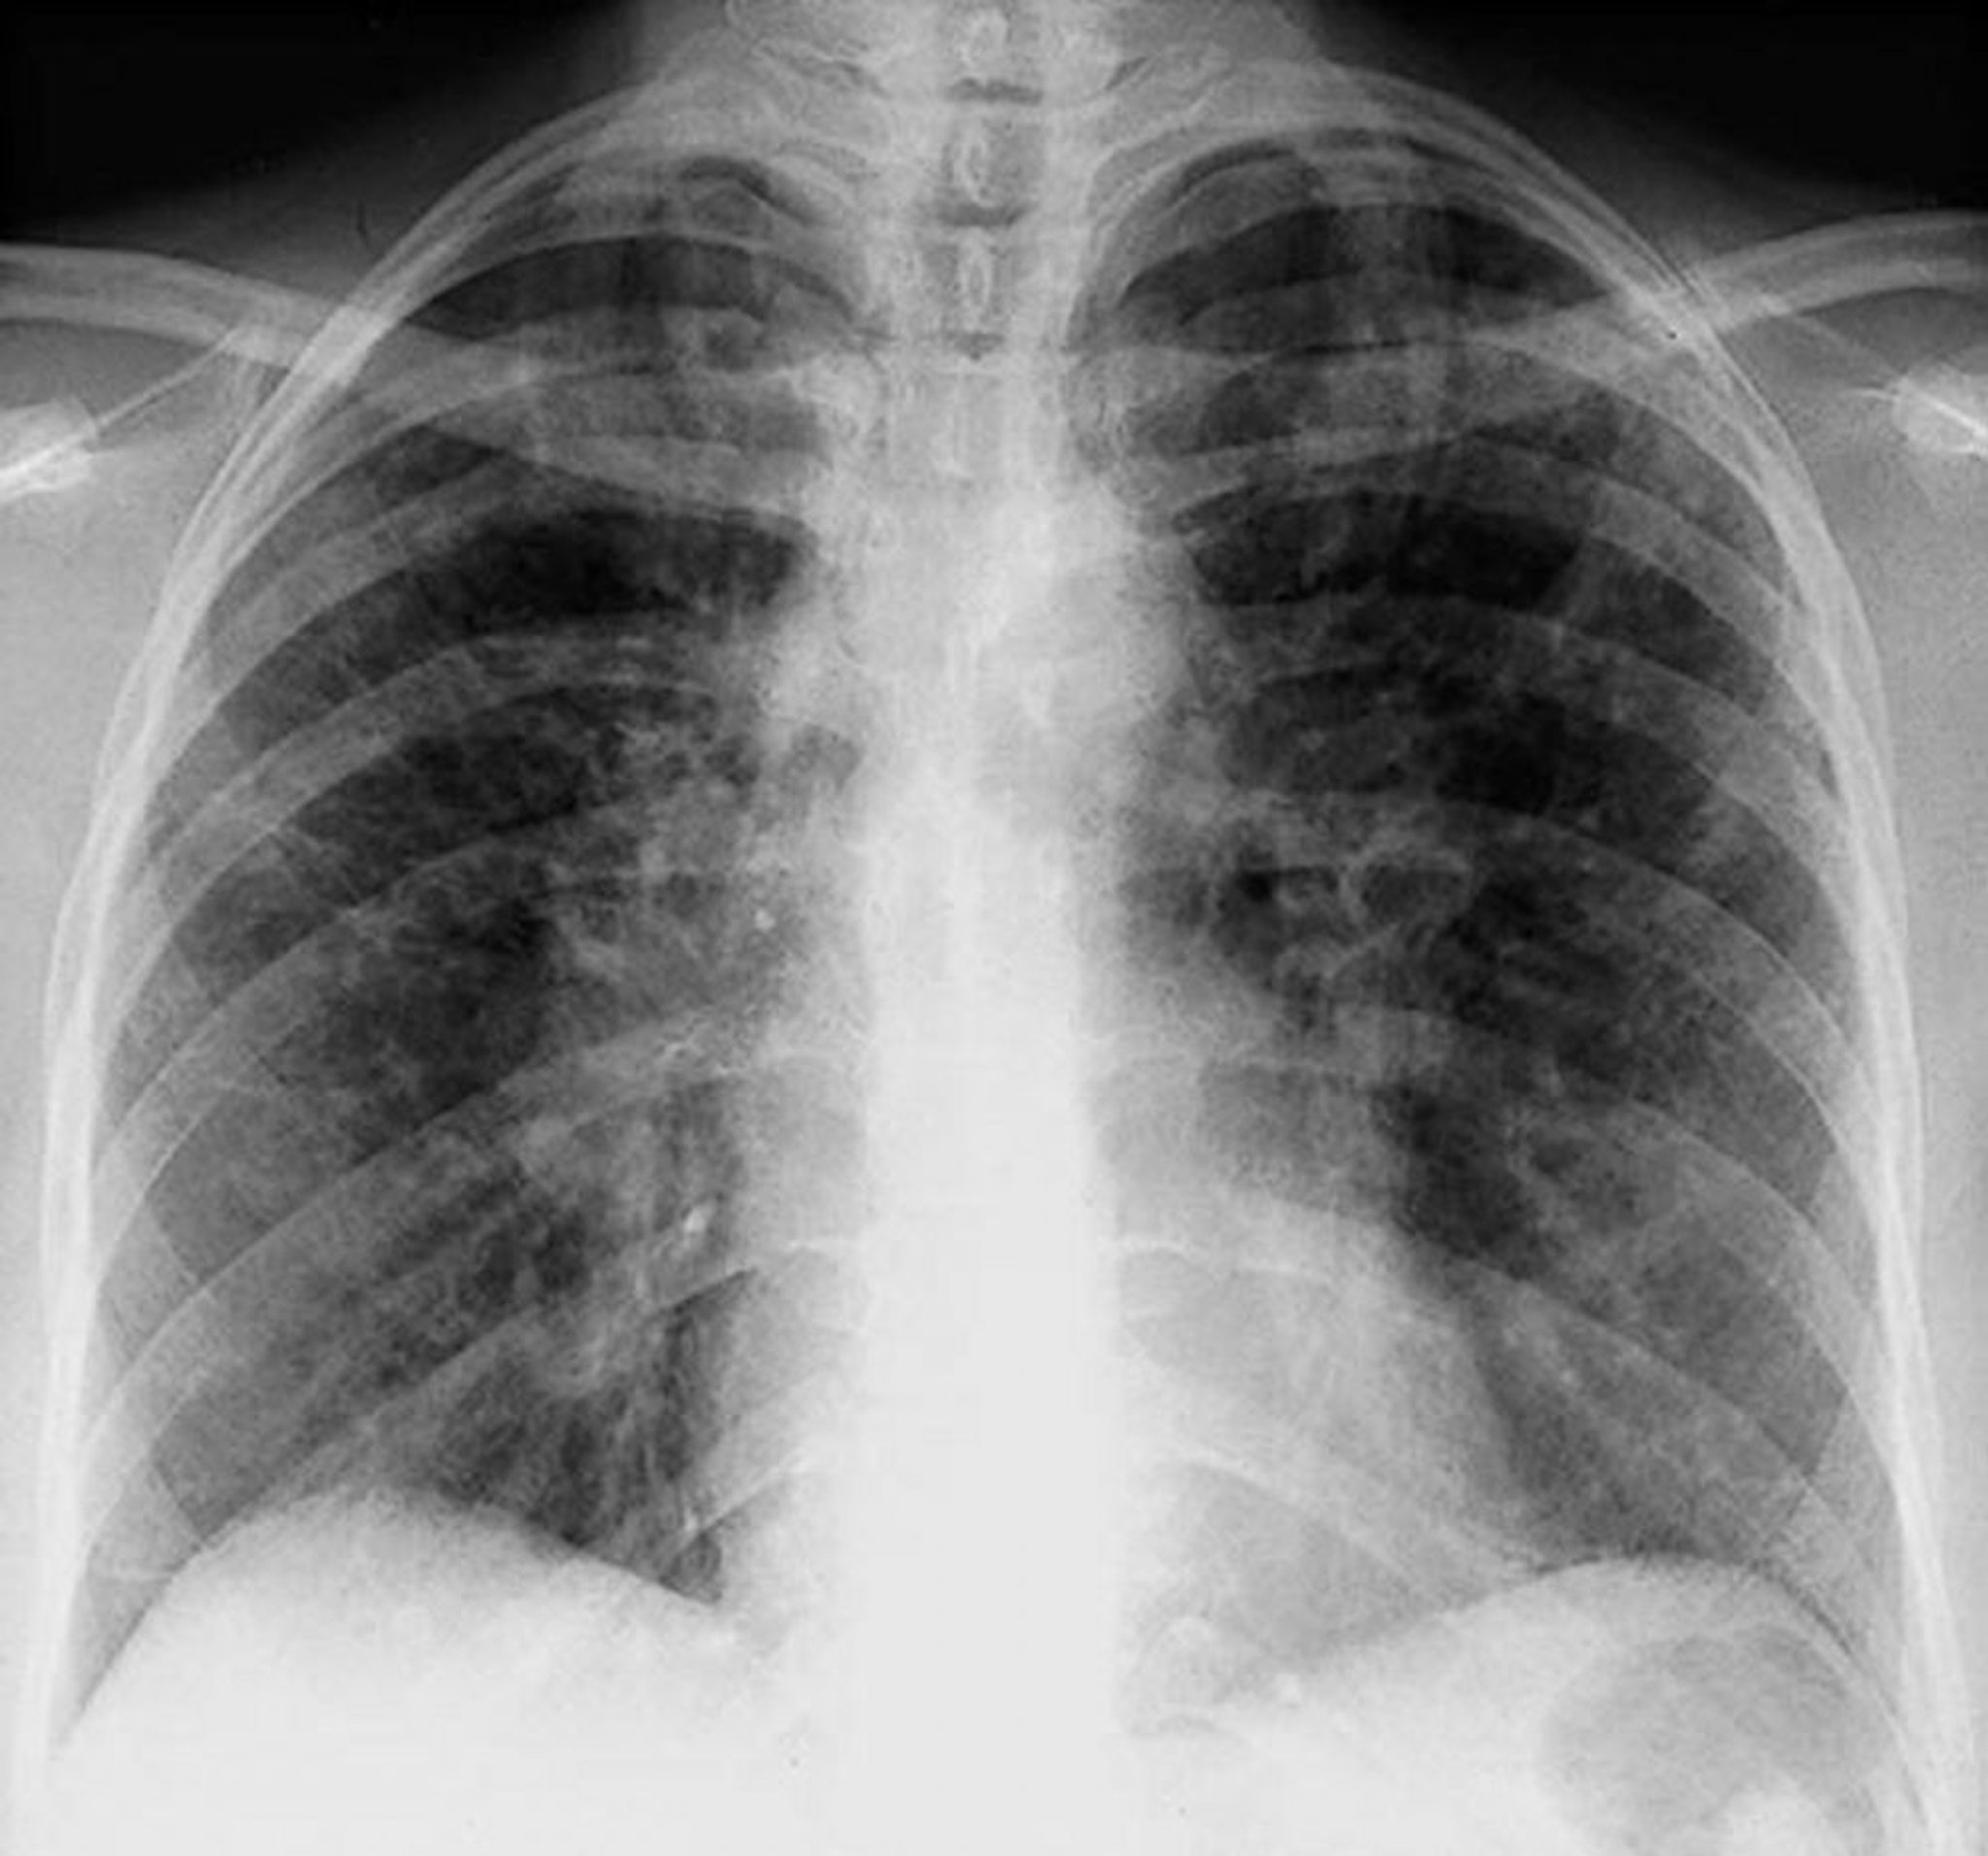

Саркоидоз — стадия II

Двусторонняя корневая лимфаденопатия с интерстициальными помутнениями при II стадии саркоидоза.

By permission of the publisher. Из Tanoue L, Elias J. In Bone's Atlas of Pulmonary and Critical Care Medicine. Edited by J Crapo. Philadelphia, Current Medicine, 2005.